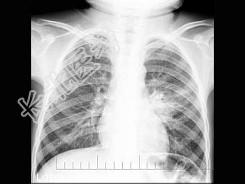

- 单项选择题男,3岁, 咳嗽、低热2周余,不咯血、咳痰, X线检查如图,最可能的诊断是 ( )

A、左肺炎症

B、左肺结核(Ⅰ型)

C、左肺结核(Ⅱ型)

D、左肺结核(Ⅲ型)

E、肺癌